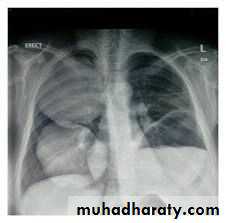

1. CXR 2. CT scan

1) well defined circular or oval homogenous opacity

thoracic surgery